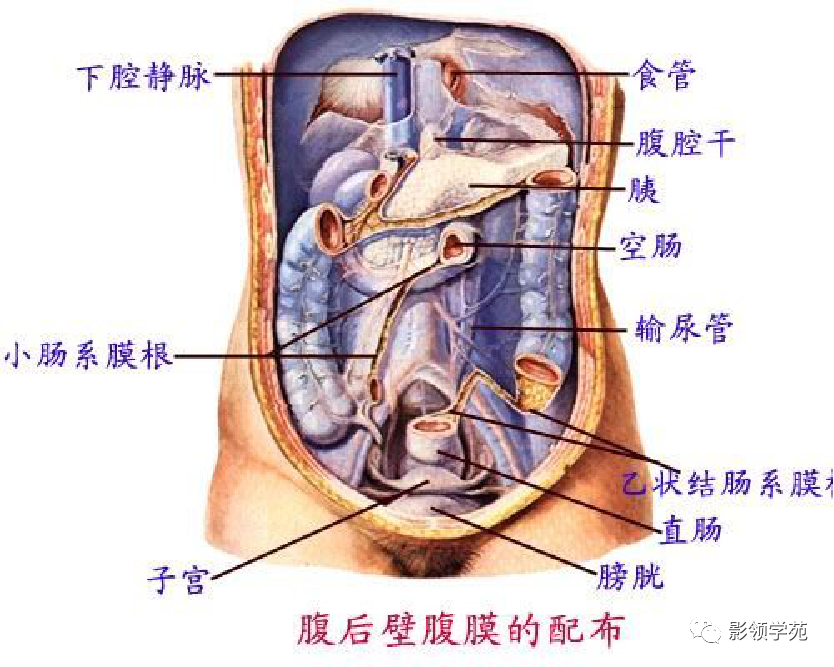

腹部动静脉

腹部动静脉